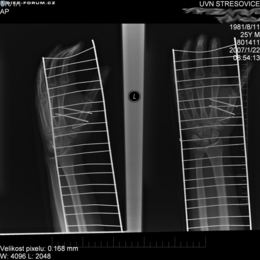

Před vytažením DHS